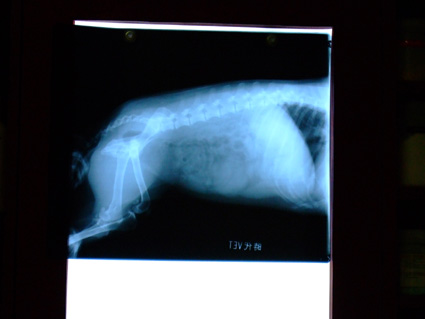

然後再帶球球照X光,確認膀胱和腎臟等器官有沒有結石.

結果也是非常OK~

因此,醫生認為,球球只是單純的細菌性感染.